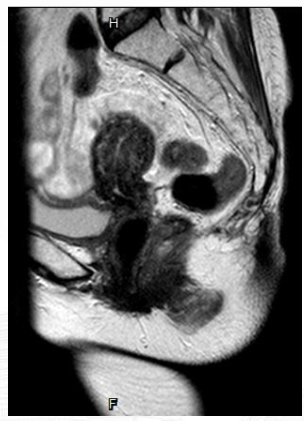

2025 年7月8日颅脑 MRI 提示左侧额叶 3.5×2.5cm 团块影,边界不清,增强扫描不均匀明显强化,与邻近脑膜分界不清,周围见斑片状水肿影,邻近左侧侧脑室受压变窄,局部中线结构稍右移约 0.6cm,提示疾病复发。

2025年7月24日起启用艾托组合抗体 5mg/Kg + 贝伐珠单抗 q3w 维持治疗,截至 2025年11月7日已完成 6 次用药,目前仍在治疗随访中。疗效评价:2025年10月16日颅脑 MRI 复查示左侧额叶转移灶缩小至 1.7×1.1cm,周围脑水肿减轻,疗效评价为 PR,目前仍在持续治疗中。治疗期间患者仅出现 1 级甲状腺功能减退、1 级白细胞减少及 1 级贫血,无严重不良反应,血象维持正常。